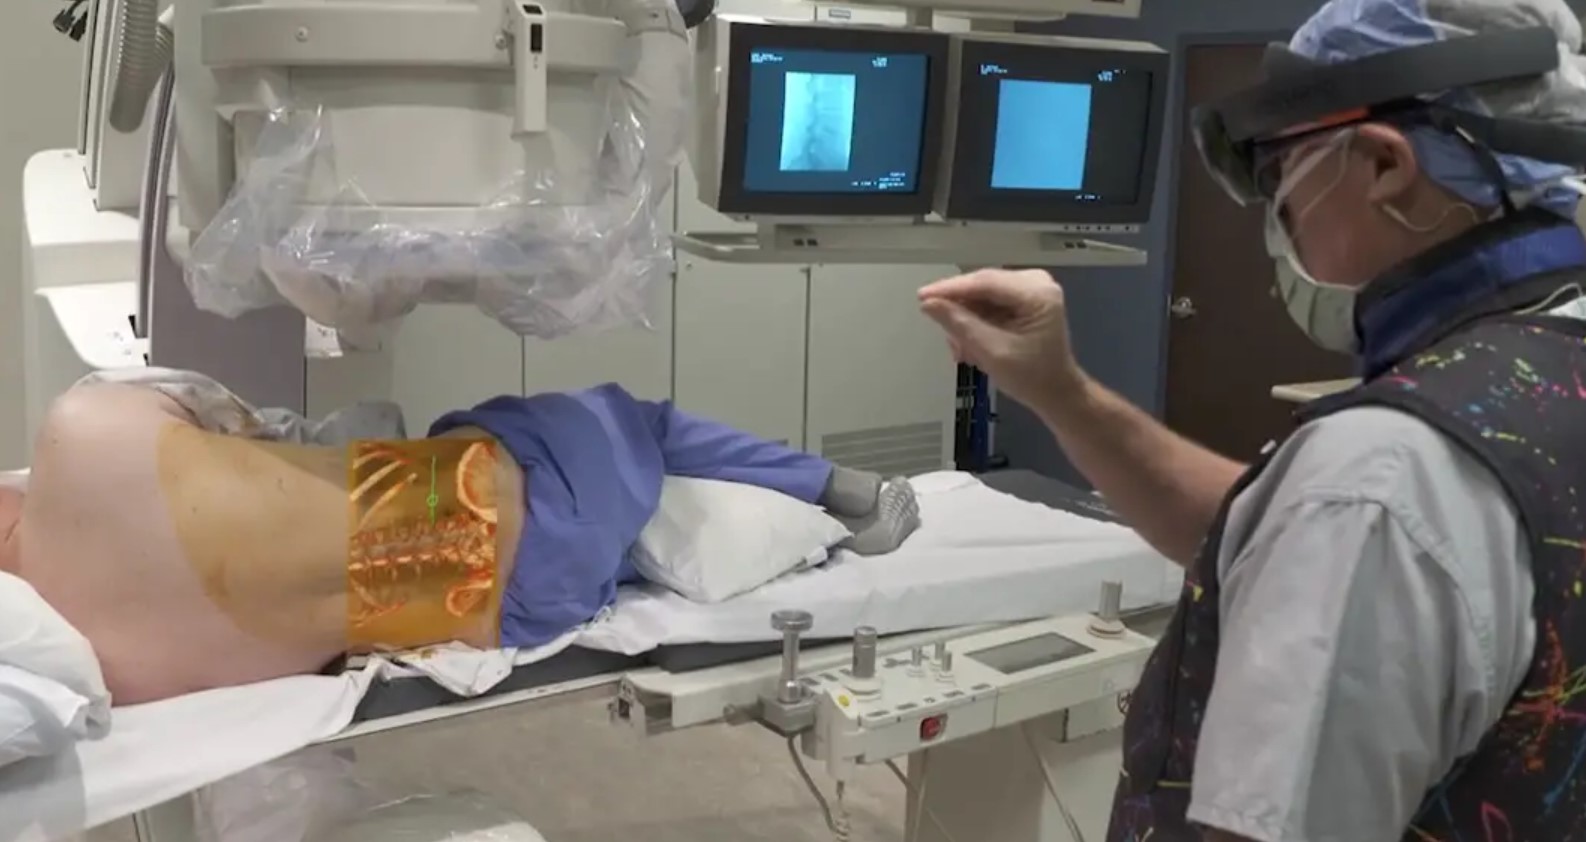

One of the most advanced HoloLens systems for medical imaging has been built by NOVARAD, see Figure 4, in the USA. Their product renders patients’ medical images (CTs, MRIs) in 3D and presents them in an interactive manner, also giving medical personnel the possibility to interact with the imaging data as well as see it displayed in the anatomically correct location on the patient.

In the case of MR (ex: HoloLens), the possibility of co-registration of the medical image to the real patient’s image gives the impression of seeing into the patient, creating a live perception of the medical image inside the patient [84]. This allows better precision of surgeon’s intervention, as seen in Figure 4.